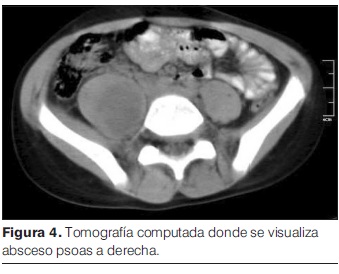

Se inicia tratamiento con clindamicina i/v que recibe por 12 días, solicitando a las 24 horas del ingreso TC de abdomen y pelvis (figura 4) que informa a nivel de psoas derecho extensa colección de 12 cm en sentido céfalo-caudal x 4cm x 3cm en sus ejes transversos.